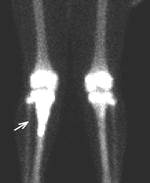

1 2 3

Рис.5. 1 – сцинтиграмма| коленных суставов; 2 – ПЭТ коленных суставов; 3 – ПЭТ скелета.